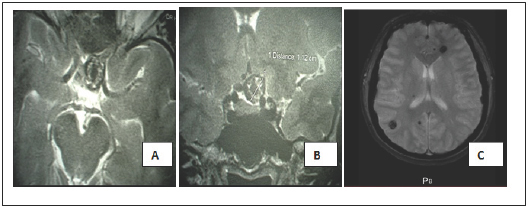

Figure 1: axial (A) and coronal (B) T2- weighted magnetic resonance images finds a cavernoma located in the left opto-chiasmatic cistern. Axial T2* (gradient echo) MRI(C) shows multiple cavernous malformations.

A 38-year-old female patient with a history of hypertension had visual blurring associated with headaches that had been progressing for a year. An ophthalmologic examination found a left pre-chiasmatic retrobulbar neuropathy with visual evoked potentials and visual acuity 10/10 in the left eye and right eye, a scotoma in the internal upper quadrant of the left eye, without ocular fundus abnormalities. Magnetic resonance imaging (MRI) revealed multiple cerebral cavernous malformations (CCMs), including one in the suprasellar region, a left frontal location, a right parietal and temporal location (Figure 1) and >was normal. A definitive surgery of the symptomatic cavernoma was performed through a left sub-frontal approach and found a cavernous lesion at the left optic nerve junction and optic chiasm (Figure 2). The removal was complete and after surgery there was a visual aggravation with a visual acuity of the left eye from 1/20 with parinaud 10 in nasal at day 6 postoperative.